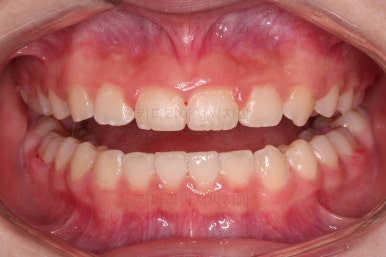

초진 시 입안의 모습입니다.

앞니가 안으로 굽어 들어간 양상인데요. 흔히 "옥니"라고 표현합니다.(뻐드렁니의 반대개념)

전반적으로 치열이 삐뚤삐뚤하고요.

오른쪽 상단 사진을 보시면 어금니의 높이와 앞니의 높이의 차이가 많이 나요.

앞니가 솟구쳐 있는 양상인데요.

그 이유 때문에 어금니로 다물었을 때 위아래 앞니가 많이 겹쳐서 아래 앞니가 아예 보이지 않는 상황이었어요.

이를 "과개교합"이라고 표현합니다.

그리고 전반적으로 아래 치열이 윗니에 비해 뒤로 밀려 있어서, 어금니의 맞물림이 좋지 못하고 듬성듬성해 보이는 상황이었어요.